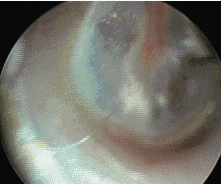

值班的主治医师仇书要通过耳镜,看到皓皓的耳朵里有只小虫子正在啃食鼓膜,也就是俗称的耳膜,这里神经丰富,超痛!

图片来源:网络

哎,也难怪别的医院不收,这只小虫子紧贴鼓膜,小孩又不配合,很容易就捅破鼓膜变聋,或者出血。